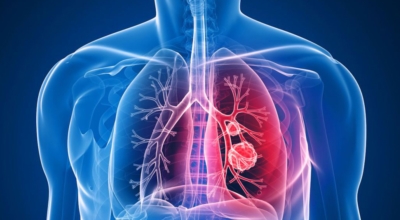

폐암은 3기 이상인 말기에 발견되는 경우가 대개라 예전에는 폐암 판정을 받으면 곧 사망이라고 부르는 말까지 있답니다. 하지만 요즘엔 의료기술이 발달하여 폐암 5년 생존율은 70%가 넘고 있어요. 무엇보다 주기적인 건강검진으로 인해서 폐암을 조기에 발견한 경우가 많아서라고 볼 수 있어요. 세세히 살펴보면 인산화효소 변이 폐암 환자의 경우 5년, 상피세포 성장인자 수용체 변이 폐암 환자의 경우 1년~3년의 생존율을 보인다고 해요. 하지만 요즘도 폐암을 3~4기에서 확진 받는 경우가 많다고 해요.

폐암 검사는 X-ray를 통해서 검사하는데 , 크기가 작거나 구석에 위치한 경우 확인이 어려운 경우도 있답니다. 그리고 조직 검사를 통해서 정확한 진단을 하게 돼요. 폐암이 발견되면 종양의 크기나 전이 여부 , 위치에 따라서 수술 여부를 결정하게 돼요.

수술 치료

악성 종양이 있는 폐의 일부를 절제하는 방법입니다. 초기에는 내시경 기구를 활용해 수술이 가능하기도 해요.

항암 치료

항암제를 이용한 치료 방법입니다. 폐암 4기 같은 경우에는 항암 화학요법이 유일한 치료방법이기도 해요. 폐암에 관해서 알아봤는데요.